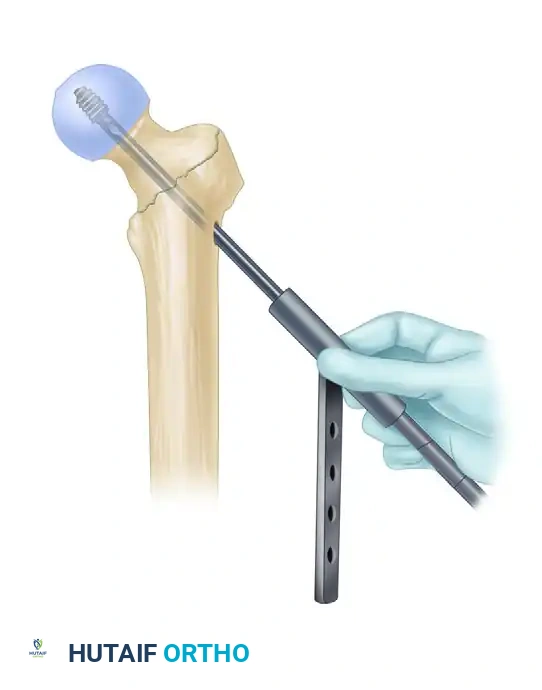

4. Intramedullary Nail Insertion

- After selecting the appropriate length and diameter, assemble the nail and the proximal drill guide securely. Ensure the targeting arm is tightly calibrated.

- Insert the nail manually. Do not use heavy mallet strikes. If the nail does not advance easily, remove it and ream an additional 0.5 mm.

- Insertion Technique: Insert the nail with the drill guide facing anteriorly (rotated 90 degrees). This utilizes the natural bow of the nail to navigate the proximal anatomy more easily. Once the nail has been inserted approximately halfway down the intramedullary canal, rotate the guide 90 degrees laterally into its final position.

- During nail advancement, continuously evaluate its trajectory with lateral fluoroscopy to avoid anterior cortical impingement.

- Insert the nail to a depth that allows for center-center positioning of the lag screw within the femoral head. Once the correct depth is achieved, remove the ball-tipped guide pin.